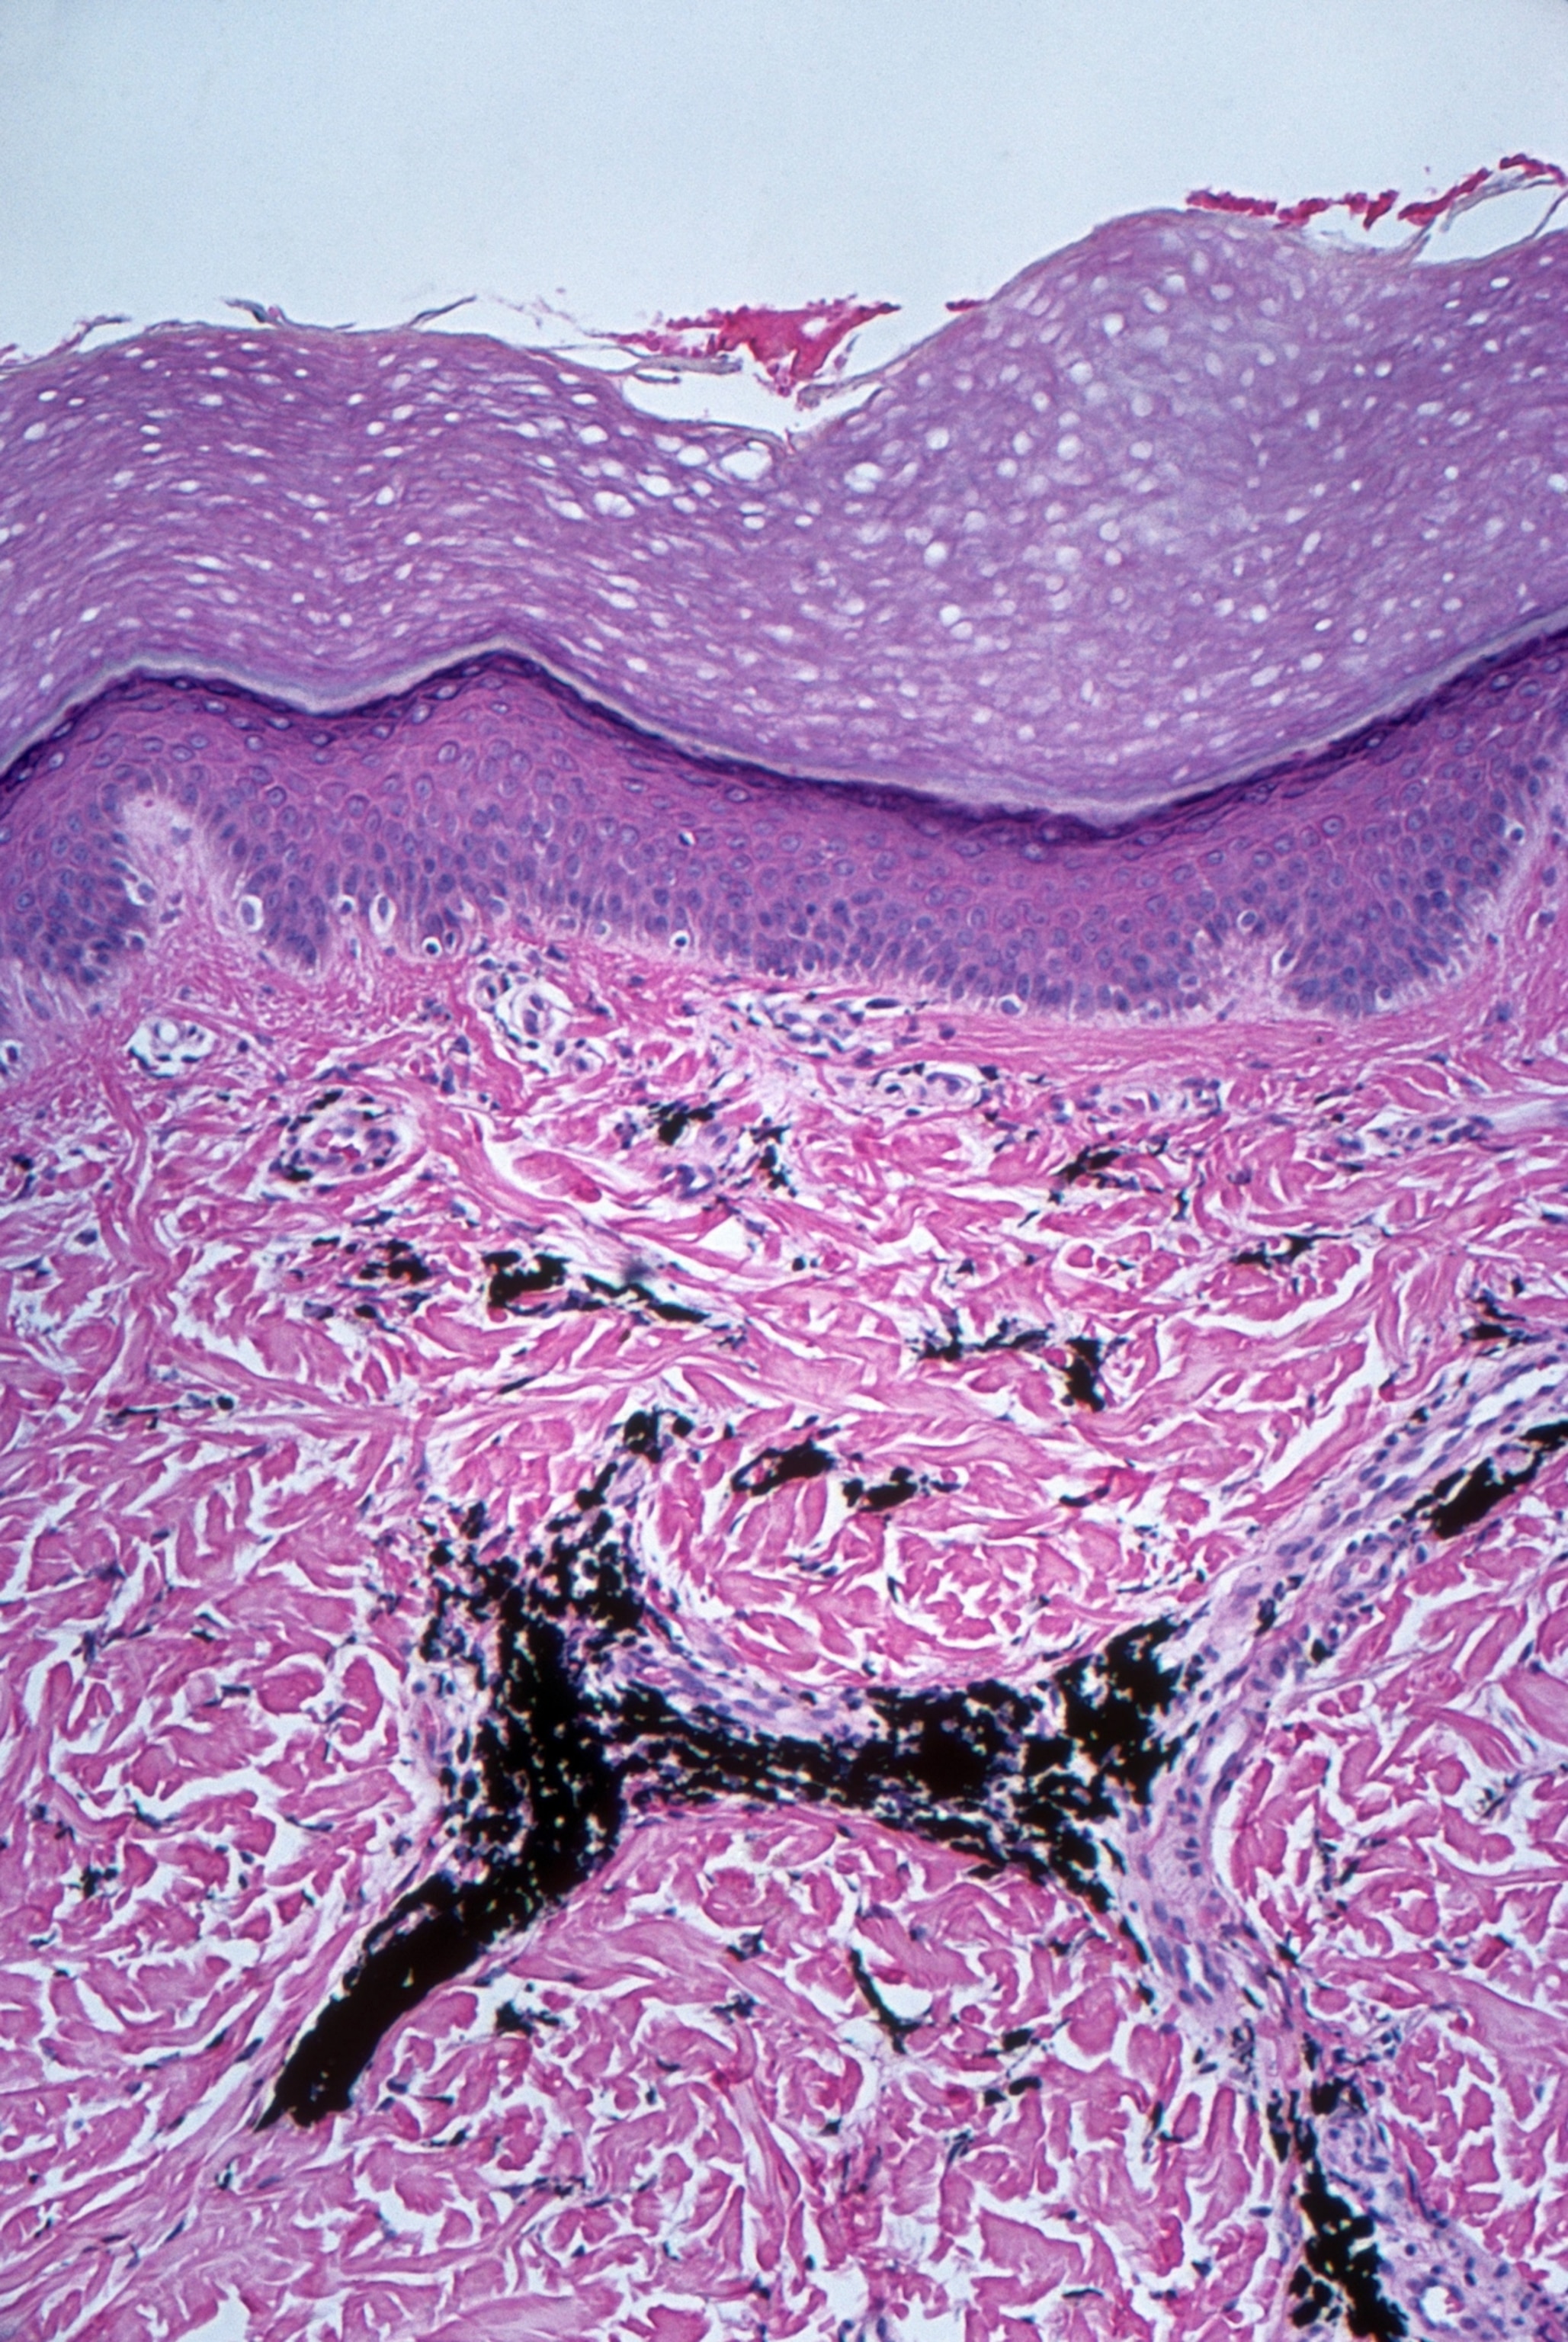

Unlike the epidermis (purple), the dermal layer (pink) of the skin is not shed when skin is tattooed. The injection of the pigment (black) triggers an immune response that results in the pigment becoming trapped inside fibroblast cells (light purple). This is what makes a tattoo permanent—and may also be why tattoos are linked to immune system changes.

Michael Abbey, Science Photo Library